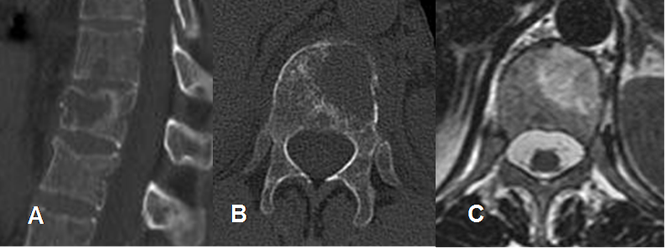

Fig 202. Cambios tratamiento.

A: TAC reconstrucción sagital, B: TAC axial y C: RM axial en T2. Lesión lítica vertebral, por mieloma.